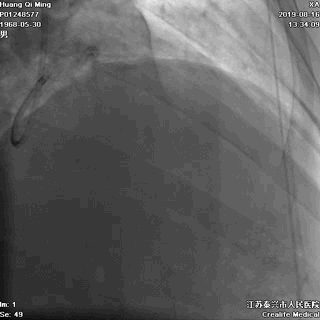

术后即刻效果满意